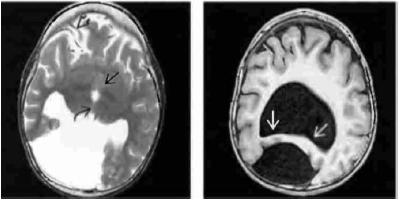

Analise as imagens abaixo.

Fonte: OSBORN, 2004.

As imagens acima correspondem a(ao):